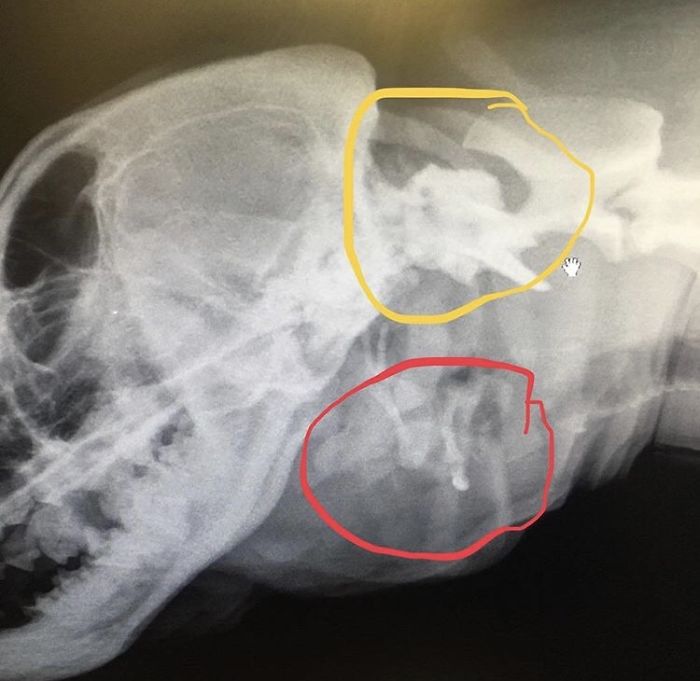

“We took more X-rays of Toad’s skull. Now that we have had Toad for a long time and learned about her issues more than when we first met her, we are able to understand the X-rays a bit better. The first image shows how wonky her skull is shaped.

“She has an extra orbital bone around her eye socket, likely from the skull of the twin she absorbed in utero, which makes her skull extra bulbous. The red circle shows two sets of hyoid bones. The yellow shows how the vertebrae aren’t attached the way they are supposed to be. The green circle shows her extra trachea, which is not fully formed.”